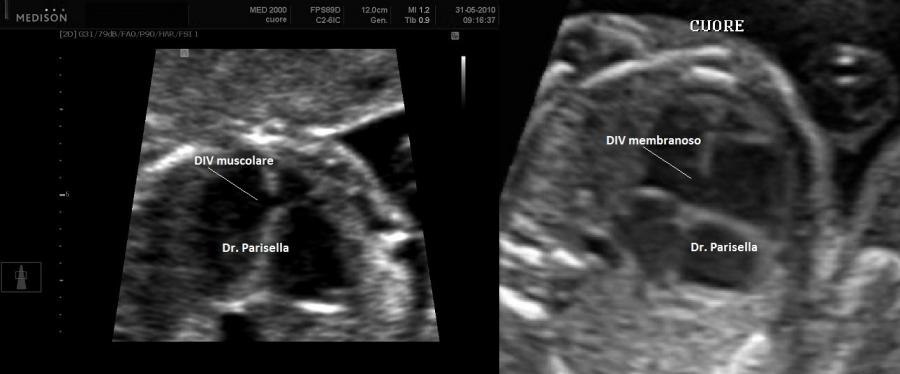

All'esame ecografico prenatale le caratteristiche che indirizzano verso la diagnosi sono:

4) la cardiopatia congenita è in genere un Difetto Interatriale.